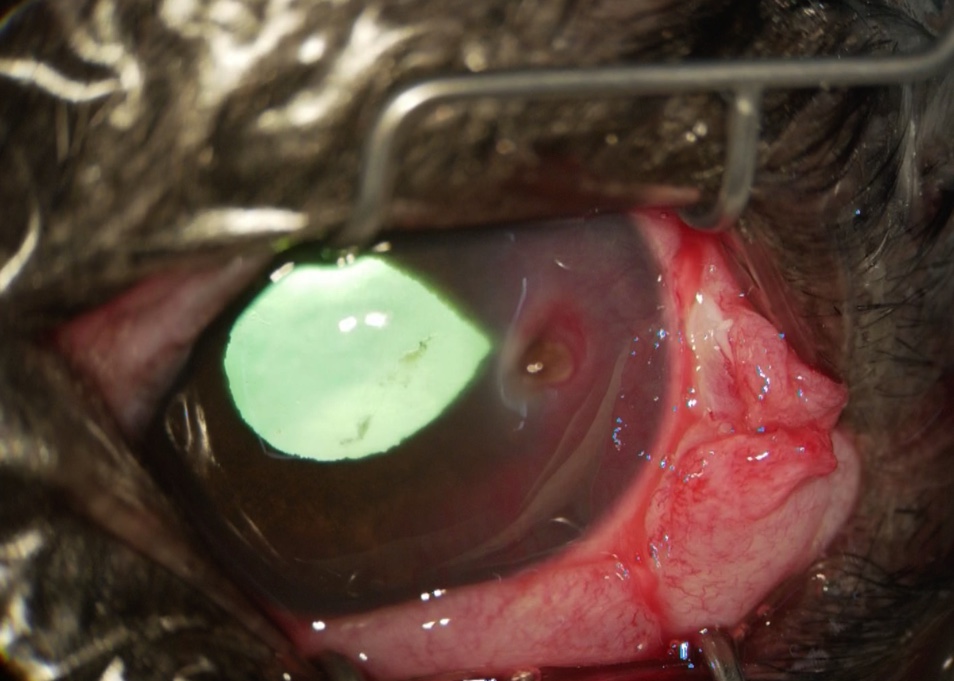

よく見ると角膜に穴が開いています。

今症例に対しては、穿孔した部位の保護、治癒促進のため、結膜フラップ術を実施しました。

穿孔部位の近くの結膜を切開し、移動して縫合しました。